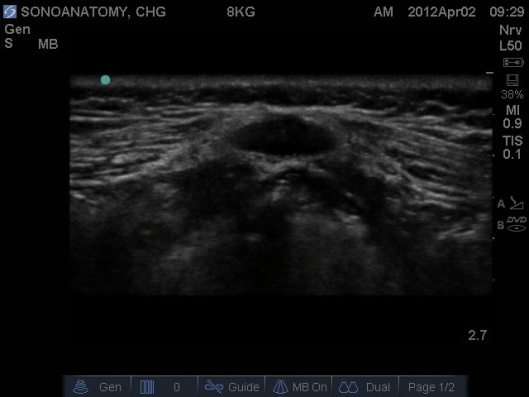

Fig 1. Ultrasound Probe in Midline Transverse position over the coccyx.

Fig 2. Ultrasound Probe in Midline Transverse position over the coccyx.

- Prior to performing the caudal a ‘Mapping’ or ‘Scout’ scan is performed to assess the position of the dural sac in relation to the sacrococcygeal membrane. The angle of needle/cannula insertion can be observed. See Figs 1-7.